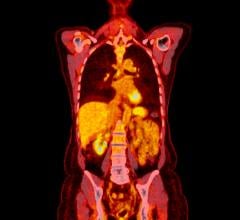

At the heart of this maladaptive immune response are microglia, immune cells in the central nervous system that can be activated to trigger neuroinflammation. For this study, researchers used positron emission tomography (PET) to measure activation of microglia by employing a molecule from E. coli bacteria called lipopolysaccharide (LPS), or endotoxin. LPS stimulates the immune system and is accompanied by a radiotracer called carbon-11 PBR28 (C-11 PBR28). This form of molecular imaging allows the minimally invasive visualization of neuroinflammation. C-11 PBR28, is injected and binds to translocator proteins expressed on activated microglia. A PET scanner can then detect the radioactive particles emitted from inside the brain, representing areas of increased microglial activation before and after immune stimulation with LPS.

The PET radiotracer C-11 PBR28 was administered to eight healthy men around the age of 25, give or take six years, followed by two separate PET scans on the same day for each subject before and after injection with LPS. Adverse symptoms were self-reported and blood samples were taken to assess levels of peripheral inflammation. Results of the study showed that administering LPS led to a substantial spike in the systemic inflammatory response and levels of reported sickness, and activated microglia in the central nervous system.